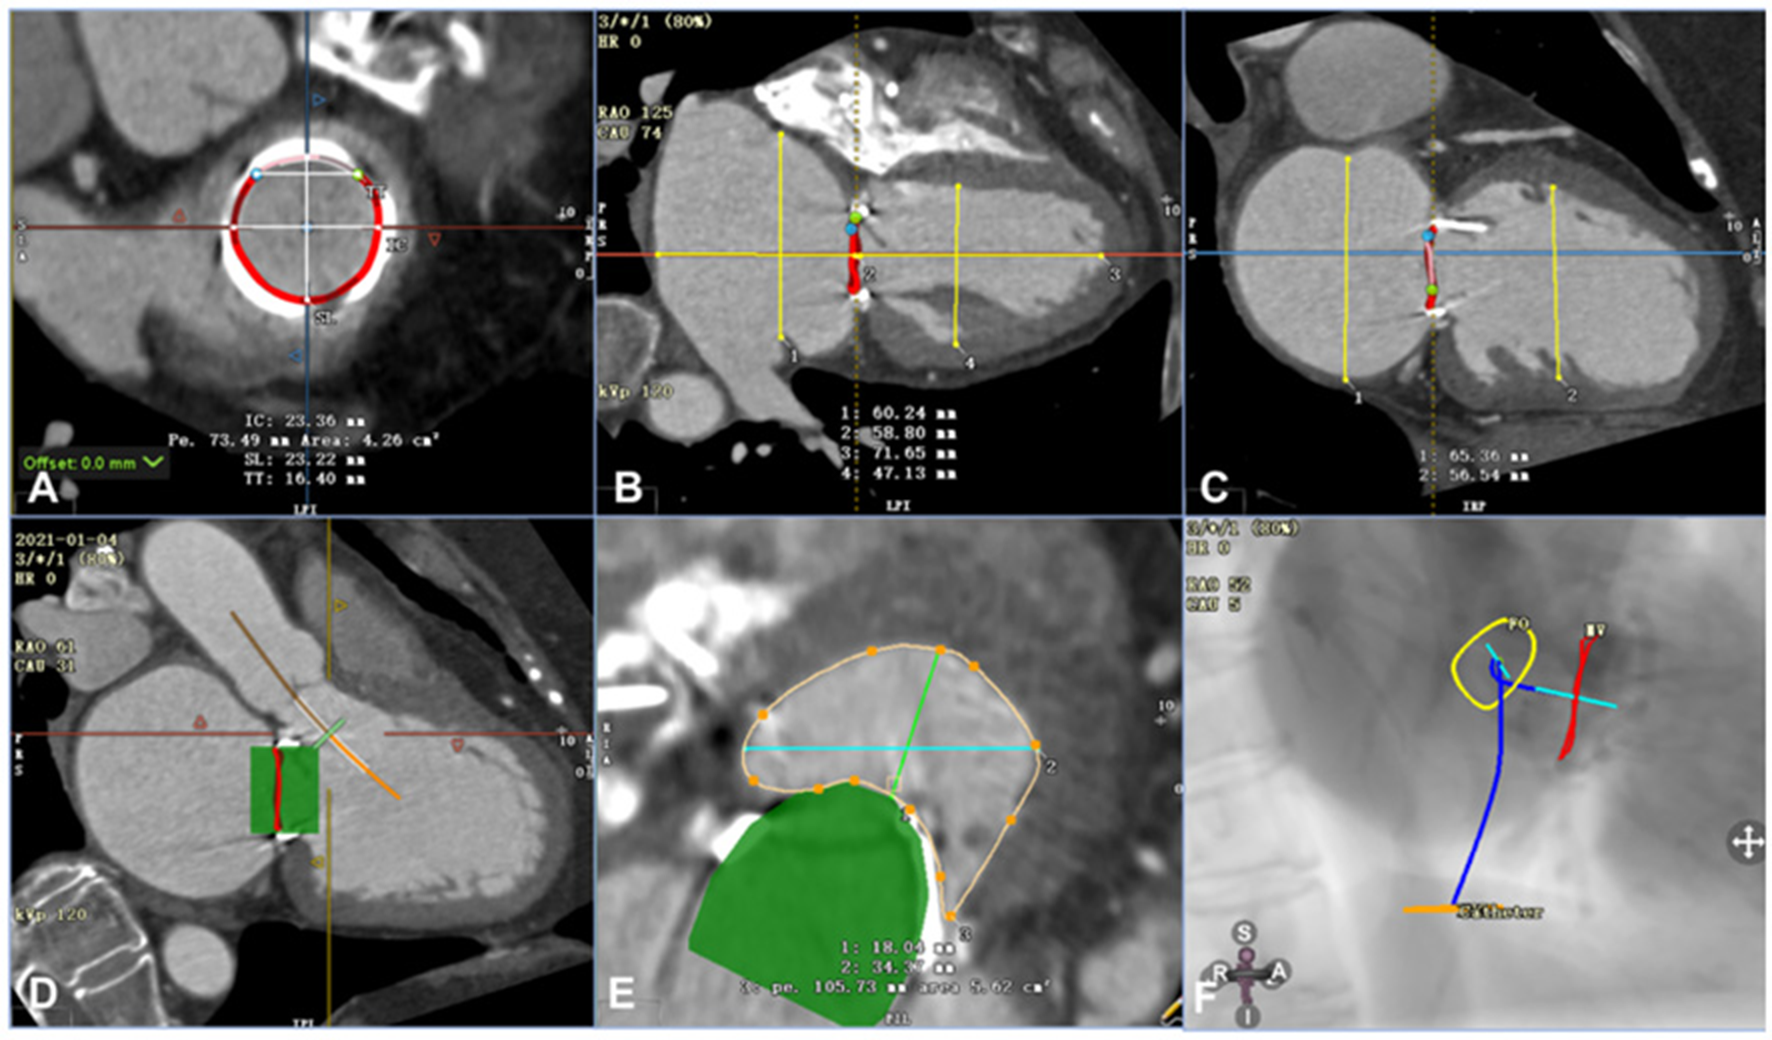

Transesophageal echocardiography (TEE) was performed on each patient before the procedure to measure and evaluate his or her anatomical abnormality. In addition, the patients' preprocedural computed tomography angiography (CTA) data were analyzed using Circle Cardiovascular Imaging CVI42 software (Calgary, Canada) (Figure 1). The inner and outer areas of the prosthetic mitral valve and the length and width of the left ventricle, the left atrium, the new left ventricular outflow tract area, and the projection angle were measured (Figure 1). Table 3 shows the preprocedural characteristics of the patients. The results showed that all the patients were suitable for the mitral V-in-V implant of the balloon-expandable valve.

Figure 1

Assessment of computed tomography angiography before the procedure using Circle Cardiovascular Imaging CVI42 software (e.g., data for patient 6). (A) Annular area of the prosthetic mitral valve was 4.26 cm2. (B) The left ventricle was 71.65 mm in the long axis and 47.13 mm in the short axis, and the left atrium was 58.80 mm in the long axis and 60.24 mm in the short axis. (C) The left and right axes of the left ventricle and left atrium were 56.54 mm and 65.36 mm, respectively. (D) By simulating a 26-mm valve, the relationship between the stent and the neo-LVOT could be observed. (E) The area of the neo-LVOT was 5.62 cm2 after simulating the process of implanting the valve. (F) The projection angle of the released valve implanted by trans-septal access is RAO52, CAU5.